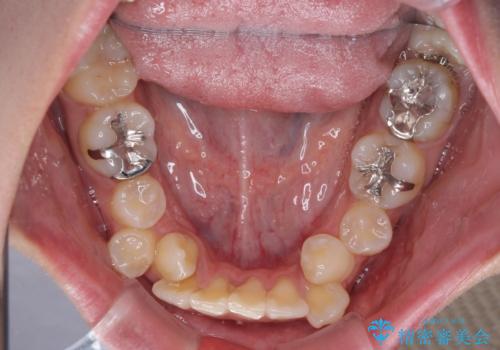

気になる八重歯を目立たない装置で改善 ハーフリンガル矯正

- 八重歯や前歯のデコボコを気にして来院された患者様です。

目立たない装置を希望されたので、上顎が裏側装置のハーフリンガルを選択し、上下左右の小臼歯(計4歯)を抜歯して矯正治療を行うこととしました。